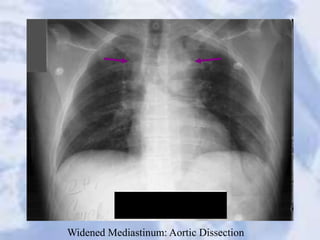

Widened Mediastinum: Aortic Dissection